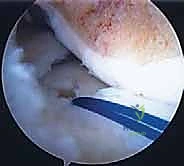

الخطوة الأولى: التنظير التشخيصي وتحضير المفصل

يبدأ الدكتور هطيف بإجراء شقوق صغيرة جداً (Portals) لإدخال كاميرا المنظار (بتقنية 4K عالية الوضوح). يتم استكشاف المفصل بالكامل. يتم تنظيف أي بقايا من الغضروف الهلالي القديم التالف، وتحضير حافة الكبسولة (Bleeding bed) لتشجيع التروية الدموية والالتئام مع الطعم الجديد.

الخطوة الخامسة: الخياطة المحيطية الدقيقة (Peripheral Suturing)

هذه هي الخطوة الأكثر حيوية. يجب خياطة محيط الغضروف الهلالي الجديد بكبسولة الركبة للمريض بشكل محكم ومتقارب جداً. يستخدم الدكتور هطيف تقنيات خياطة متعددة بالمنظار:

* تقنية من الداخل للخارج (Inside-out): تعتبر المعيار الذهبي للغضروف الهلالي، حيث يتم تمرير إبر طويلة من داخل المفصل إلى خارجه لتثبيت الغضروف بالكبسولة.

* تقنية من الخارج للداخل (Outside-in): تستخدم لتثبيت الجزء الأمامي من الغضروف.

* تقنية الخياطة الداخلية بالكامل (All-inside): تستخدم أجهزة تثبيت حديثة لبعض الأجزاء الخلفية.